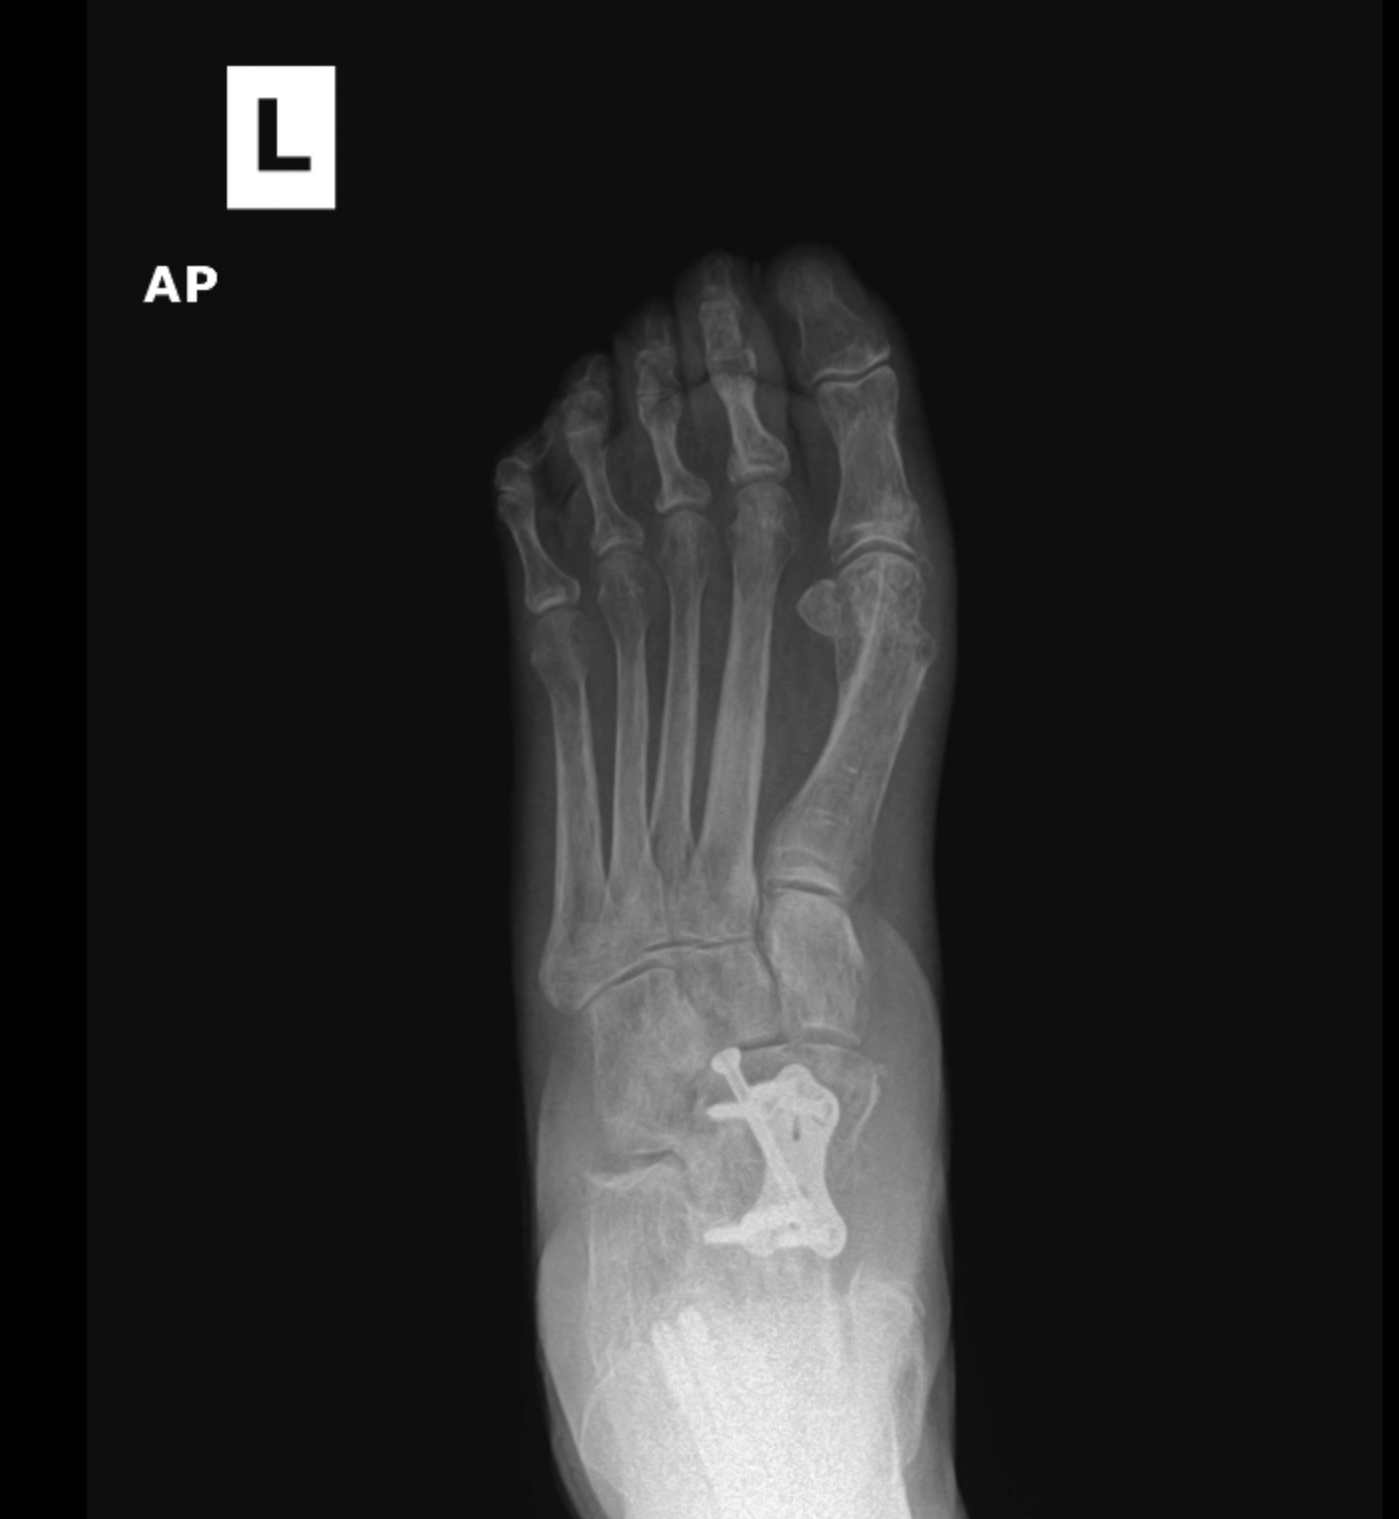

Flatfoot deformity

Patient 1

Patient 2